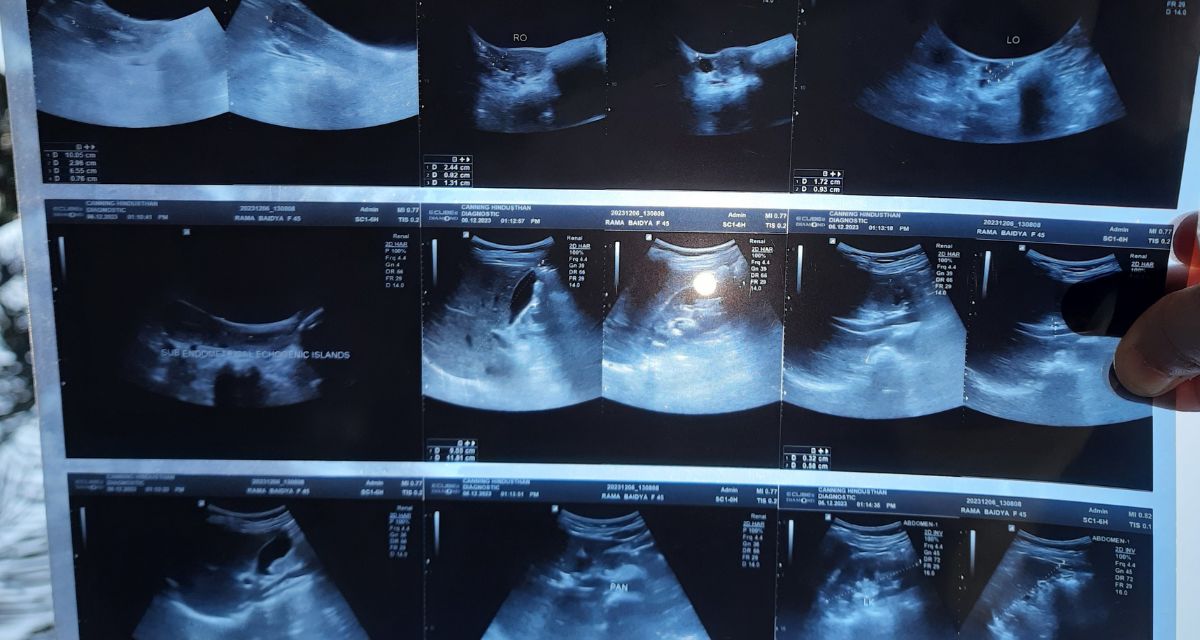

Doctors offered conflicting advice. One said the condition could still be managed with medicines. Another said surgery was the only option left. By the time Rama reached a private hospital in Canning, an ultrasound showed adenomyotic changes, an abnormal thickening of the uterine wall. Doctors explained that while adenomyosis does not directly result from urinary or vaginal infections, chronic pelvic inflammation and repeated infections can aggravate symptoms and complicate treatment, especially when infections stop responding to antibiotics. With her pain worsening and no antibiotic working anymore, she consented to the operation.